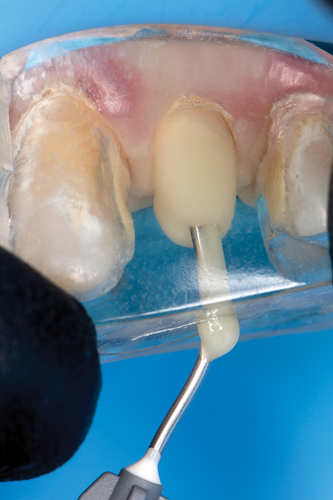

After completion of the endodontic treatment and crown lengthening to develop an ideal ferrule effect (Figure 3 through Figure 5) a diagnostic wax-up was fabricated to an ideal coronal preparation geometric shape, dimension, and height for the anticipated final composite core buildup (Figure 6). A clear polyvinyl siloxane (PVS) impression material was injected into a nonperforated tray, placed over the diagnostic wax-up, and then put into a pressure pot with cold water for 5 minutes. This procedure is aimed at reducing the potential for the formation of voids and bubbles in the impression material (Figure 7 and Figure 8). A small opening was made above the tooth to be restored using a tapered diamond bur (6847) (Figure 9). It is important to clean the internal surfaces with a microbrush to prevent silicone debris from integrating into the flowable material. Prior to the restorative procedure, a diagnostic wax-up was fabricated to the anticipated extracoronal contours for development of the final crown (Figure 10).

The clear silicone matrix was placed over the posterior segment of the maxillary arch, and an opacious A2-shaded injectable flowable universal resin composite was injected through a small opening above the preparation and fiber post (Figure 20 and Figure 21). The resin composite was cured through the clear resin matrix on the incisal, facial, and lingual aspects for 40 seconds each. Upon removal of the matrix, the excess polymerized composite resin was removed with a #12 scalpel blade, and the incisal sprue was removed using a tapered diamond finishing bur. A round, tapered diamond bur was used to establish the gingival margin (Figure 22) and a needle-shaped finishing bur was used to complete the finishing of the preparation.

Fig 8. The completed matrix, which is intended to provide a precise replication of the diagnostic wax-up.

Figure 8

Fig 20. The clear silicone matrix was placed over the posterior segment of the maxillary arch, and flowable resin composite was injected through a small opening above the preparation and fiber post.

Figure 20

Fig 21. During the injection process, the tip was removed slowly while injecting to prevent the incorporation of air bubbles.

Figure 21